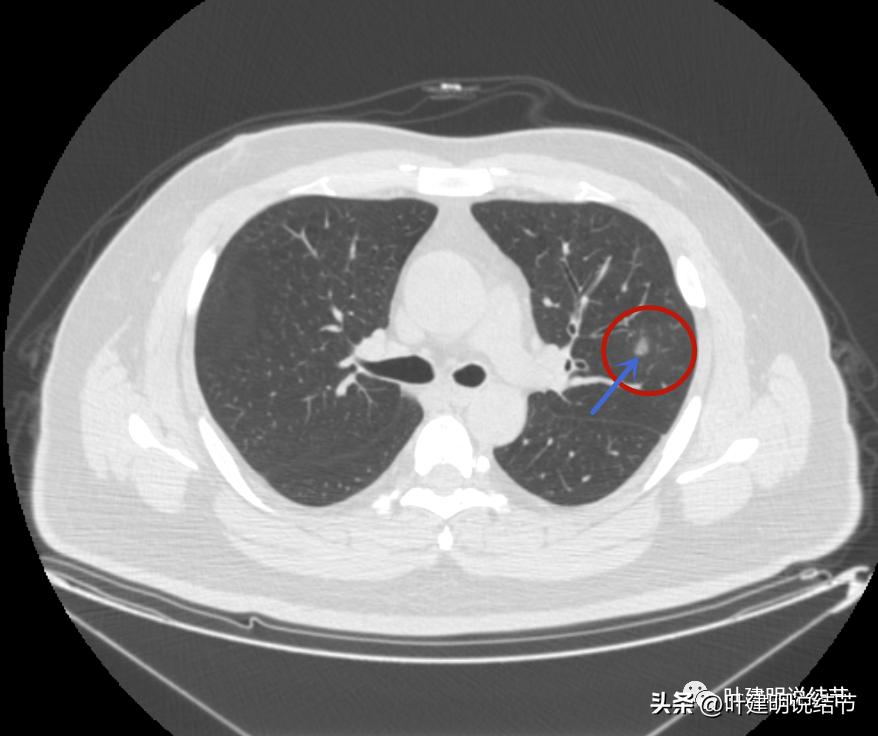

左上病灶4:

病灶出现,是淡磨玻璃影,但有微血管进入(桔色箭头)

密度稍不均,中间点状偏高密度,是不是血管?

周围微小血管好像有往病灶集中的趋势(桔色箭头)

病灶有胸膜间隙征(黄色箭头)、细毛刺样征(紫色箭头),整体轮廓较清(红色箭头)

轮廓清而密度稍不均,但总体仍应该算纯磨玻璃密度

有明显的血管穿行与细毛刺征

这个病灶也仍考虑是恶性范畴的,只是风险较病灶2与病灶3为低。也就是说看了细节与所有层面的信息,仍基本上认为四个病灶都是肿瘤范畴的,病灶1与病灶4大概浸润前病变可能性大,病灶2与病灶3则至少微浸润,基本以浸润性腺癌可能性大,不过不太能理解的有两点:一是病灶太集中;二是有的层面似有卫星灶。当然病灶2与病灶3感觉磨玻璃的成分偏少了些,也可作为疑惑之处。